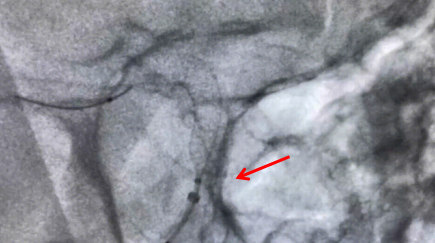

手術中釋放支架圖片

牟科杰主任醫師介紹,顱內動脈瘤是血管壁形成的囊狀突起,是顱內“不定時炸彈”,動脈瘤介入治療,已經從彈簧圈栓塞時代進展到了血流導向密網支架治療的時代。傳統的治療方法是單純彈簧圈栓塞或支架輔助彈簧圈栓塞或開顱夾閉,但對于一些瘤頸寬、瘤體大、多發動脈瘤的患者,血流導向裝置成為一種最佳的治療手段。通過血流導向密網支架的釋放,重建血管內血流方向,使動脈瘤血栓化,促進血管內皮的再生及修復,最終使瘤頸閉合而治愈。血管重建技術是顱內動脈瘤血管內治療的重大突破,它使得一些復雜的腦動脈瘤治療風險相對降低,術后復發率低,同時也讓手術時間大為縮短,為復雜動脈瘤的治療帶來了全新方法。4月19日上午,手術歷時兩小時順利完成。